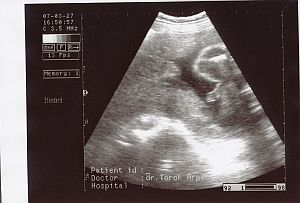

Ez a kis arca, szembööl. Kép

Ez az elsöö kukis képe 27. hetesen :-)

Kép

Második kukis kép 29 hetesen :-) Kép

ès itt van öö, profilbol. Kép

Nagyon utálta az uh-t, a kis keze ott van az arcocskája elöött. Remélem, hogy minden kivehetöö.

Kata: Nagyon édi!! A 29 hetest nem tom kivenni :oops:

Ott rajta van az egész lábacskája, ahogy kicsit összehúzza és jobb oldalt, a combjánál látszanak a kis heréi. :D